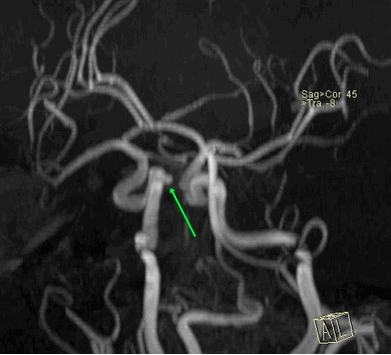

Рисунок 1. МРТ сосудов головного мозга. Мешотчатая аневризма интраклиноидного отдела правой ВСА.

Аневризма. Выбухание сосудистой стенки в одну или сразу несколько сторон. Обусловлено снижением эластичности артерии, систематическим повышением локального давления, дегенерацией слоев сосуда. Состояние опасное и зачастую незаметное. Пациент не ощущает расстройства. Результатом может стать разрыв артерии и массивное внутреннее кровотечение. МРТ четко показывает сосудистые аномалии даже на ранней стадии.